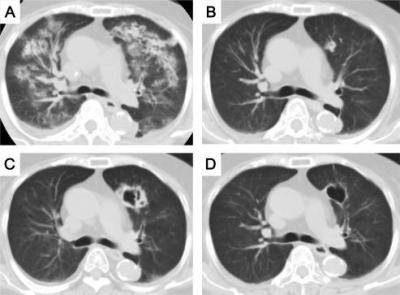

क्रॉनिक ऑब्स्ट्रक्टिव पल्मोनरी डिजीजचा सामना करत असलेल्या दोन्ही रुग्णांचा उपचारादरम्यान मृत्यू झाला. एस्परजिलियस लेंटुलस फुफ्फुसावर परिणाम करतं. २००५ मध्ये वैद्यकीय जगताला या फंगसची औषध पटली. तेव्हापासून आतापर्यंत अनेक देशांमध्ये एस्परजिलियस लेंटुलसचे रुग्ण आढळून आले आहेत.

पहिल्या रुग्णावर एका खासगी रुग्णालयात उपचार सुरू होते. मात्र प्रकृतीत सुधारणा न झाल्यानं त्यांना एम्समध्ये हलवण्यात आलं. त्यांना Amphotericin B आणि ओरल Voriconazole इंजेक्शन्स देण्यात आली. मात्र महिन्याभरानंतरही त्यांची प्रकृती सुधारली नाही आणि त्यांचा मृत्यू झाला.

दुसऱ्या रुग्णाला ताप, खोकला आणि श्वास घेण्यास त्रास सुरू होता. त्यासाठी त्याला एम्समध्ये दाखल करण्यात आलं. त्यालाही Amphotericin B देण्यात आलं. मात्र आठवड्याभरातच शरीरातील अनेक अवयव निकामी झाल्यानं त्याचा मृत्यू झाला.